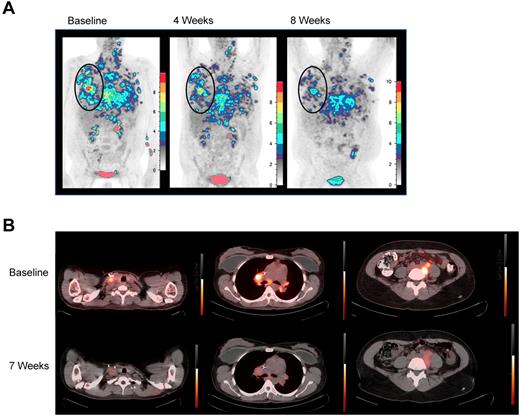

Five patients were evaluable for response. PN1, PN2, and PN3 experienced unabated, rapid progression, and clinical deterioration requiring additional treatment and/or initiation of hospice before 4-week restaging. Four of the 5 subsequent patients maintained stable disease through at least 2 evaluations and each manifested some evidence of antitumor activity. PN6 and PN8 demonstrated transient responses by positron emission tomography (PET), with decreased 18FDG uptake in all measurable lesions (Figure 1), and PN4 and PN7 demonstrated mixed responses. PN5 may also have had an antitumor effect from TDL, if pneumonitis reflected a tumor-directed immune response. Interestingly, both PET responses were in patients with Hodgkin lymphoma (HL) whose tumors were enriched with donor-derived reactive cells. Plausibly, in HL, gain of type 1 effector function and retained tumor homing permitted infused TDL to transiently disrupt the HL microenvironment.17,18

18FDG-PET responses. (A) 18FDG-PET before and at 4 and 8 weeks after TDL. PN6, a 36-year-old with primary-refractory HL with unabated disease progression following myeloablative conditioning and a 6 of 6 HLA-matched sibling-donor AlloSCT with posttransplantation in vivo T-cell depletion with cyclophosphamide. Transient responses followed radiation and gemcitabine, vinorelbine, and liposomal doxorubicin therapies. Twenty-eight months post-AlloSCT, TDL were generated from a right axillary tumor harvest and 26.3 × 106 TDL/kg were infused. Moderate pain and tenderness at sites of chest wall tumor and worsening of pleural effusions developed 1 week after infusion. At restaging, 18FDG-PET-CT demonstrated decreasing standardize uptake values (SUV) in all lesions over 3 consecutive months. By 4 months, however, PET showed increasing SUV in prior sites of disease, which correlated with clinical progression. Shown are coronal maximum intensity projection (MIP) images with a cutoff intensity of 2.5 SUV. (B) Transverse 18FDG-PET-CT fusion images demonstrate decreased SUV in PN8, a 35-year-old with relapsed HL, whose disease progressed from best partial response 6 months after reduced-intensity conditioning and a T-cell replete, 6 of 6 HLA-matched sibling-donor AlloSCT. The patient was treated with vinblastine and subsequently with 3 cycles of dose-adjusted EPOCH (etoposide, vincristine, adriamycin, prednisone, and cyclophosphamide) plus DLI. Seventy months from AlloSCT, TDL were generated from a right axillary tumor harvest, and 91.2 × 106 TDL/kg were infused. Grade 2 cytokine release syndrome (culture-negative fevers to 39.5°C, mild hypotension, and tachycardia) was observed from 4 to 24 hours after infusion. 18FDG-PET-CT was stable at 4 weeks, then demonstrated decrease in SUV in multiple sites of disease at 2 months; tumor size was stable by CT. At 4 months, although PET-CT did not show clear progression, the patient developed severe radicular pain associated with tumor-involved cervical lymph nodes requiring additional therapy.